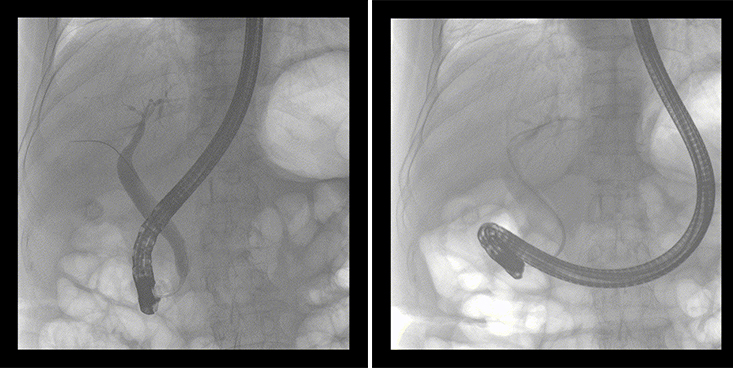

一位86歲的女性患者近來(lái)出現(xiàn)腹痛,入院后CT檢查并結(jié)合臨床表現(xiàn)被診斷為急性膽囊炎伴膽囊結(jié)石。經(jīng)專家團(tuán)隊(duì)協(xié)商并與患者家屬溝通,決定對(duì)患者實(shí)施經(jīng)內(nèi)窺鏡逆行胰膽管造影(ERCP)。

ERCP(經(jīng)十二指腸鏡下逆行胰膽管造影)現(xiàn)已成為比較成熟的微創(chuàng)介入技術(shù),被廣泛的應(yīng)用于臨床,ERCP也是消化內(nèi)鏡領(lǐng)域難度大、風(fēng)險(xiǎn)大、技術(shù)復(fù)雜的微創(chuàng)手術(shù),其并發(fā)癥多為致命性,ERCP手術(shù)對(duì)醫(yī)生的要求很高,因此,ERCP醫(yī)生又被稱為“刀尖上的舞者”。因?yàn)槭中g(shù)難度較大,過(guò)程復(fù)雜,需要C形臂精準(zhǔn)的配合,對(duì)影像清晰度的要求也非常高。

普愛醫(yī)療移動(dòng)式平板中C為本次ERCP手術(shù)提供實(shí)時(shí)無(wú)損高清影像,幫助醫(yī)生精準(zhǔn)定位。“成像效果非常棒!完全不輸國(guó)際大牌的醫(yī)學(xué)影像設(shè)備……”鼓樓醫(yī)院江北國(guó)際醫(yī)院內(nèi)鏡中心手術(shù)團(tuán)隊(duì)對(duì)普愛醫(yī)療移動(dòng)式平板中C的成像效果給與了高度的評(píng)價(jià)。

在消化內(nèi)科主任的領(lǐng)導(dǎo)和多科室全力配合下,南京鼓樓醫(yī)院江北國(guó)際醫(yī)院成功完成了首例ERCP手術(shù)。